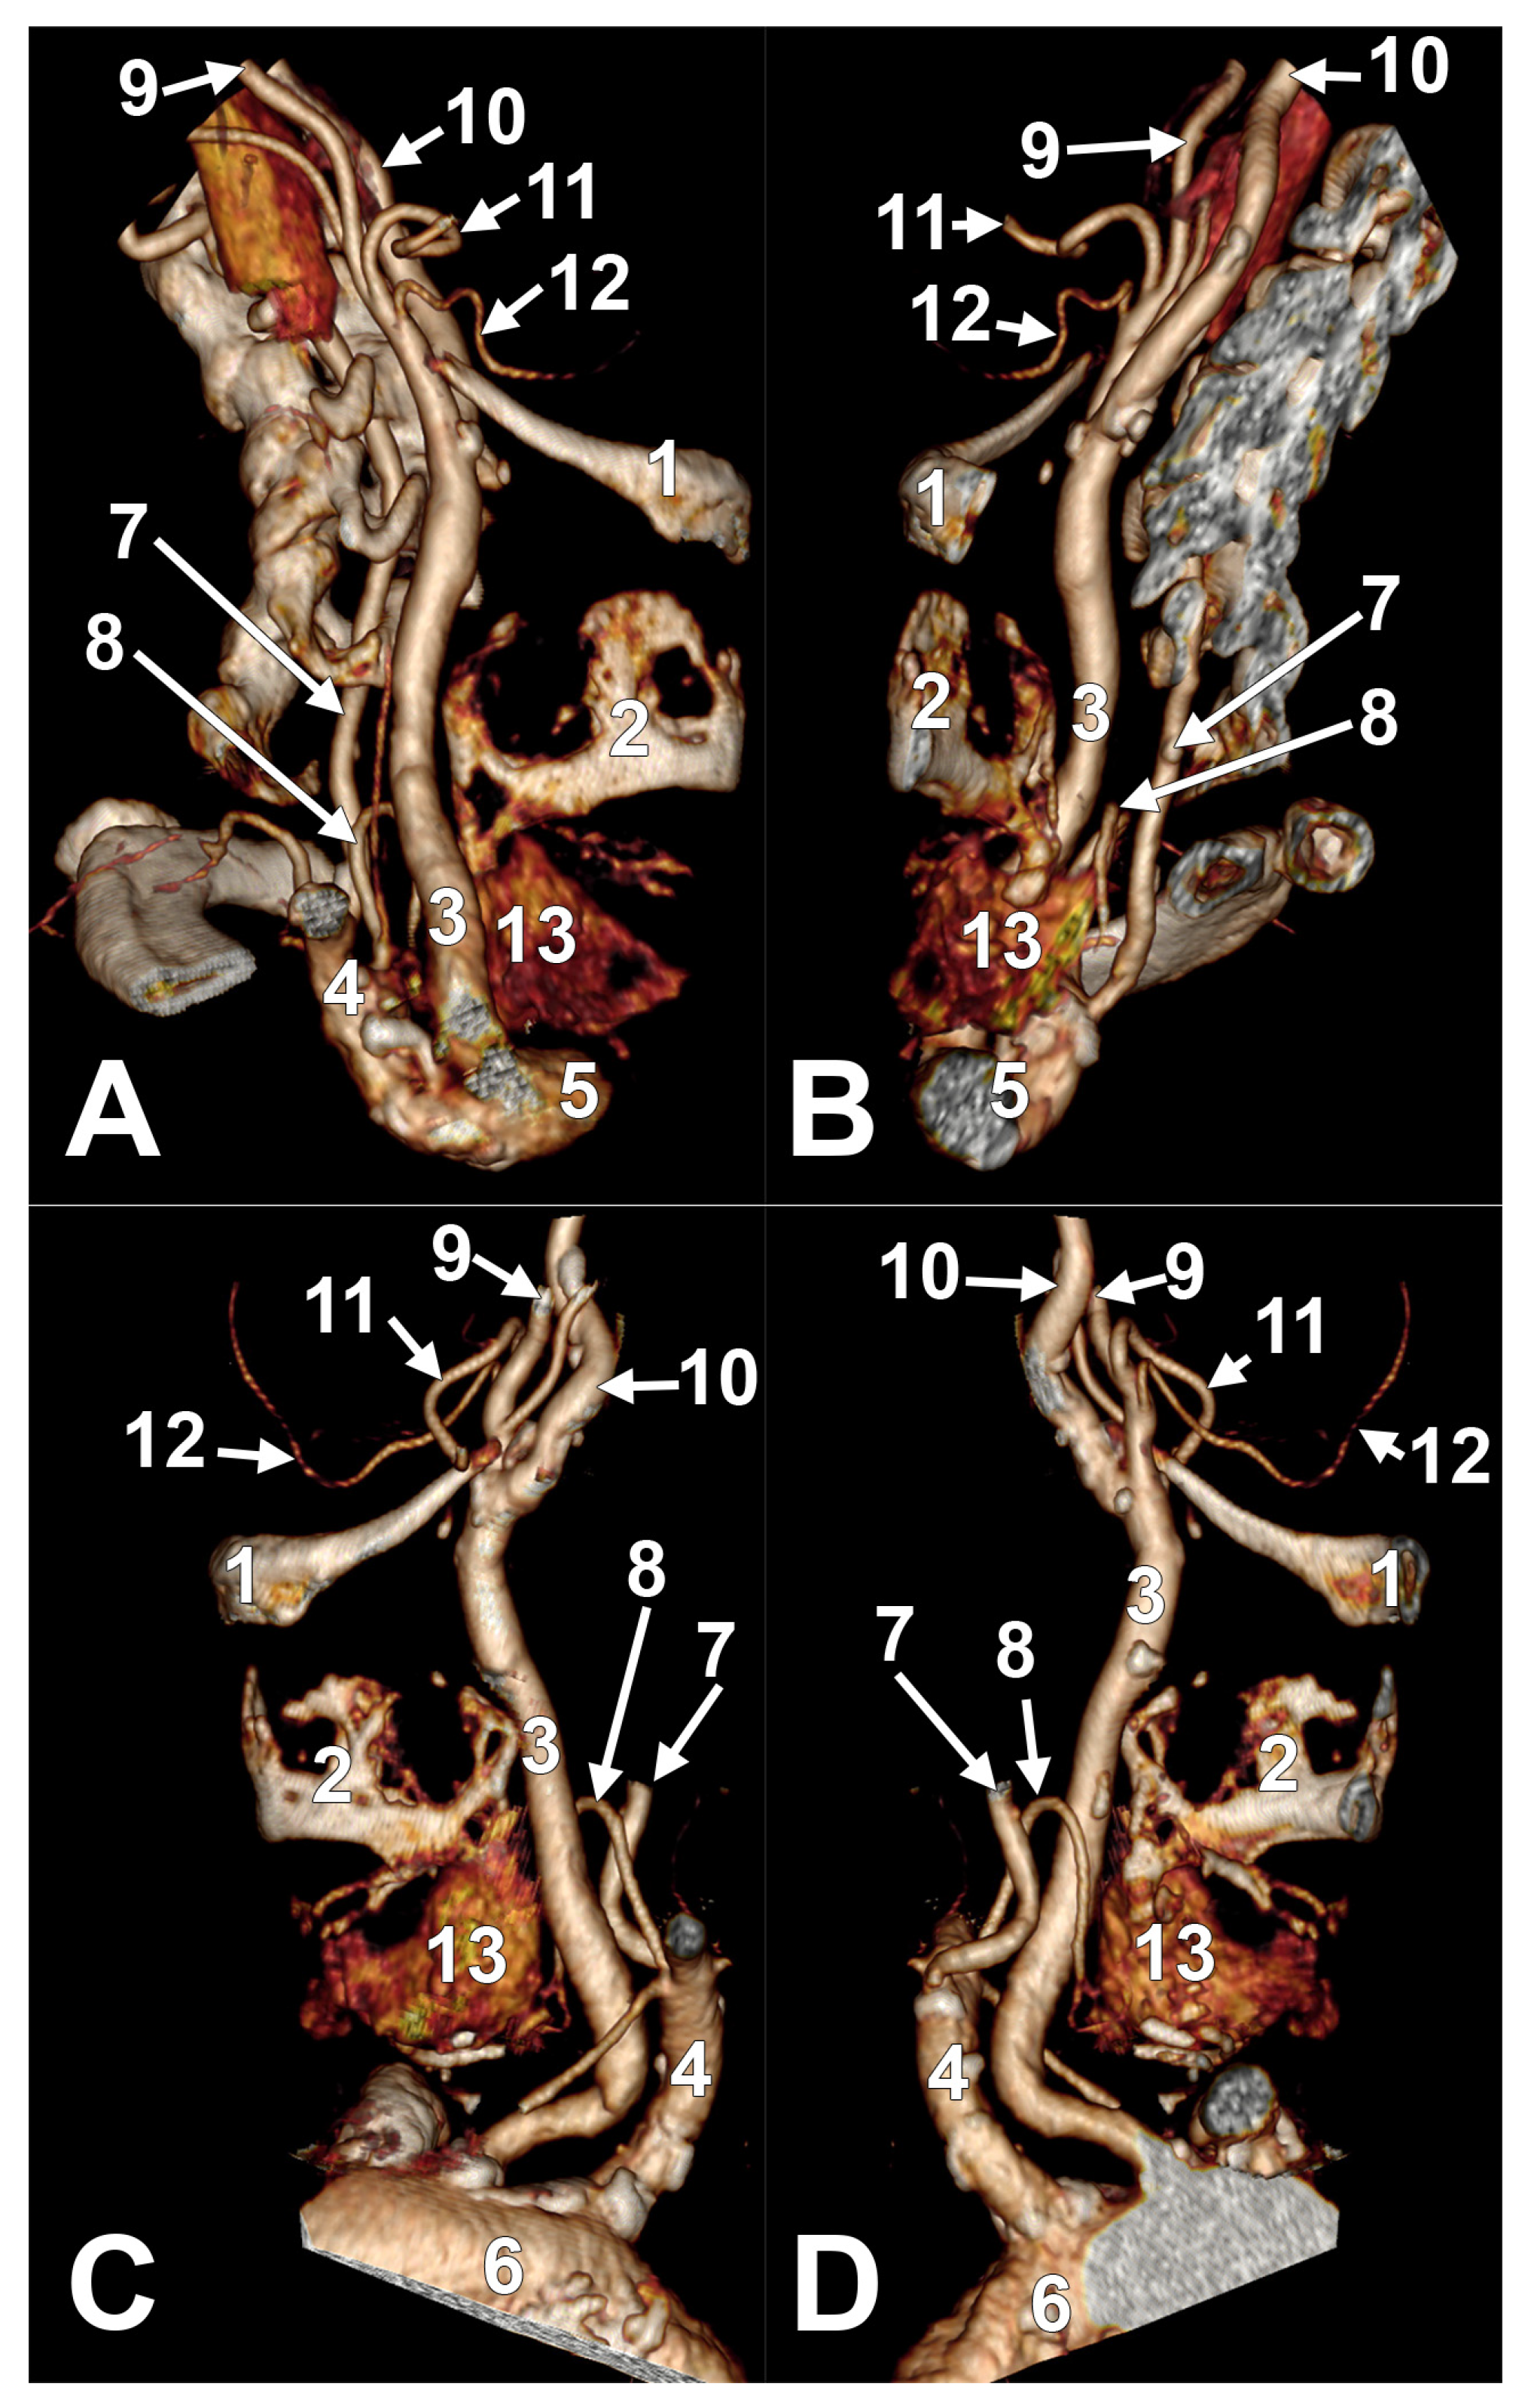

Appendix A.2. Supplemental Figures